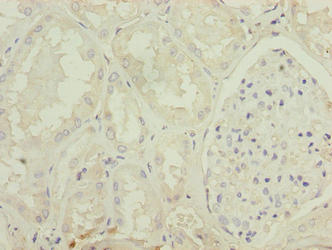

- 胰腺病理:MSTN基因突變的犢牛會(huì)發(fā)生胰腺腺泡細(xì)胞壞死以及炎癥細(xì)胞浸潤,從而引發(fā)致死性胰腺炎,為MSTN參與胰腺穩(wěn)態(tài)調(diào)控提供了有力證據(jù) [1]。